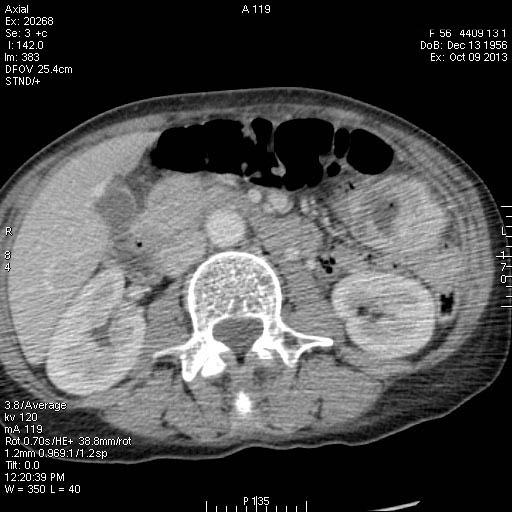

Женщина средних лет поступила в хирургическое отделение с кишечным кровотечением.

Пальпируется образование в мезогастриуме слева. При УЗИ определяется тумор, не связанный с толстой кишкой.

КТ

Колоноскопия - тумор не обнаружен.

Операция - обнаружена опухоль тонкой кишки, предположительно гемангиома, выполнена резекция части кишки.

Гистологический ответ - GIST.